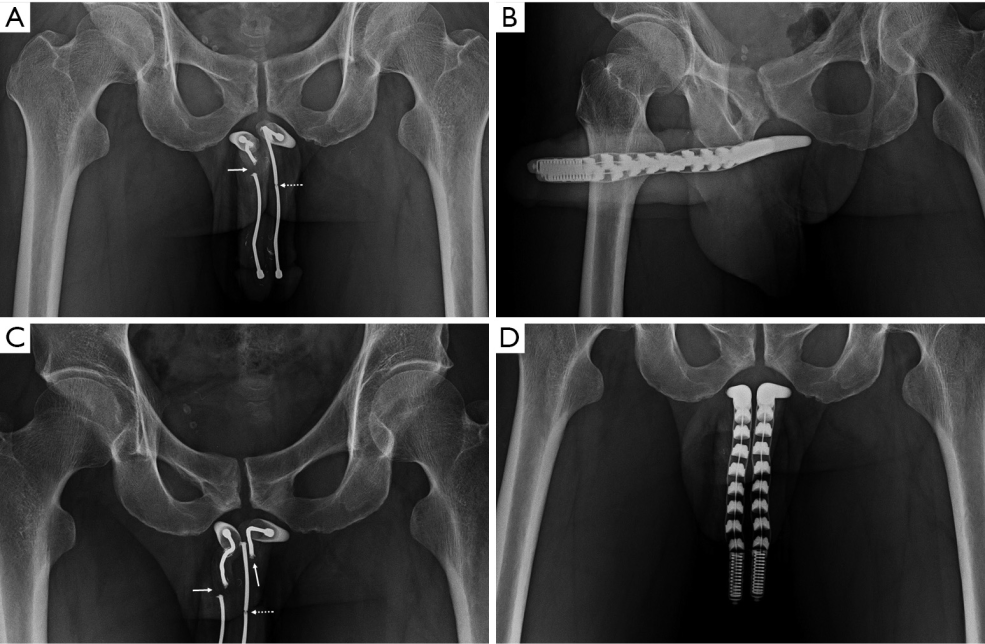

AMS 700 CX